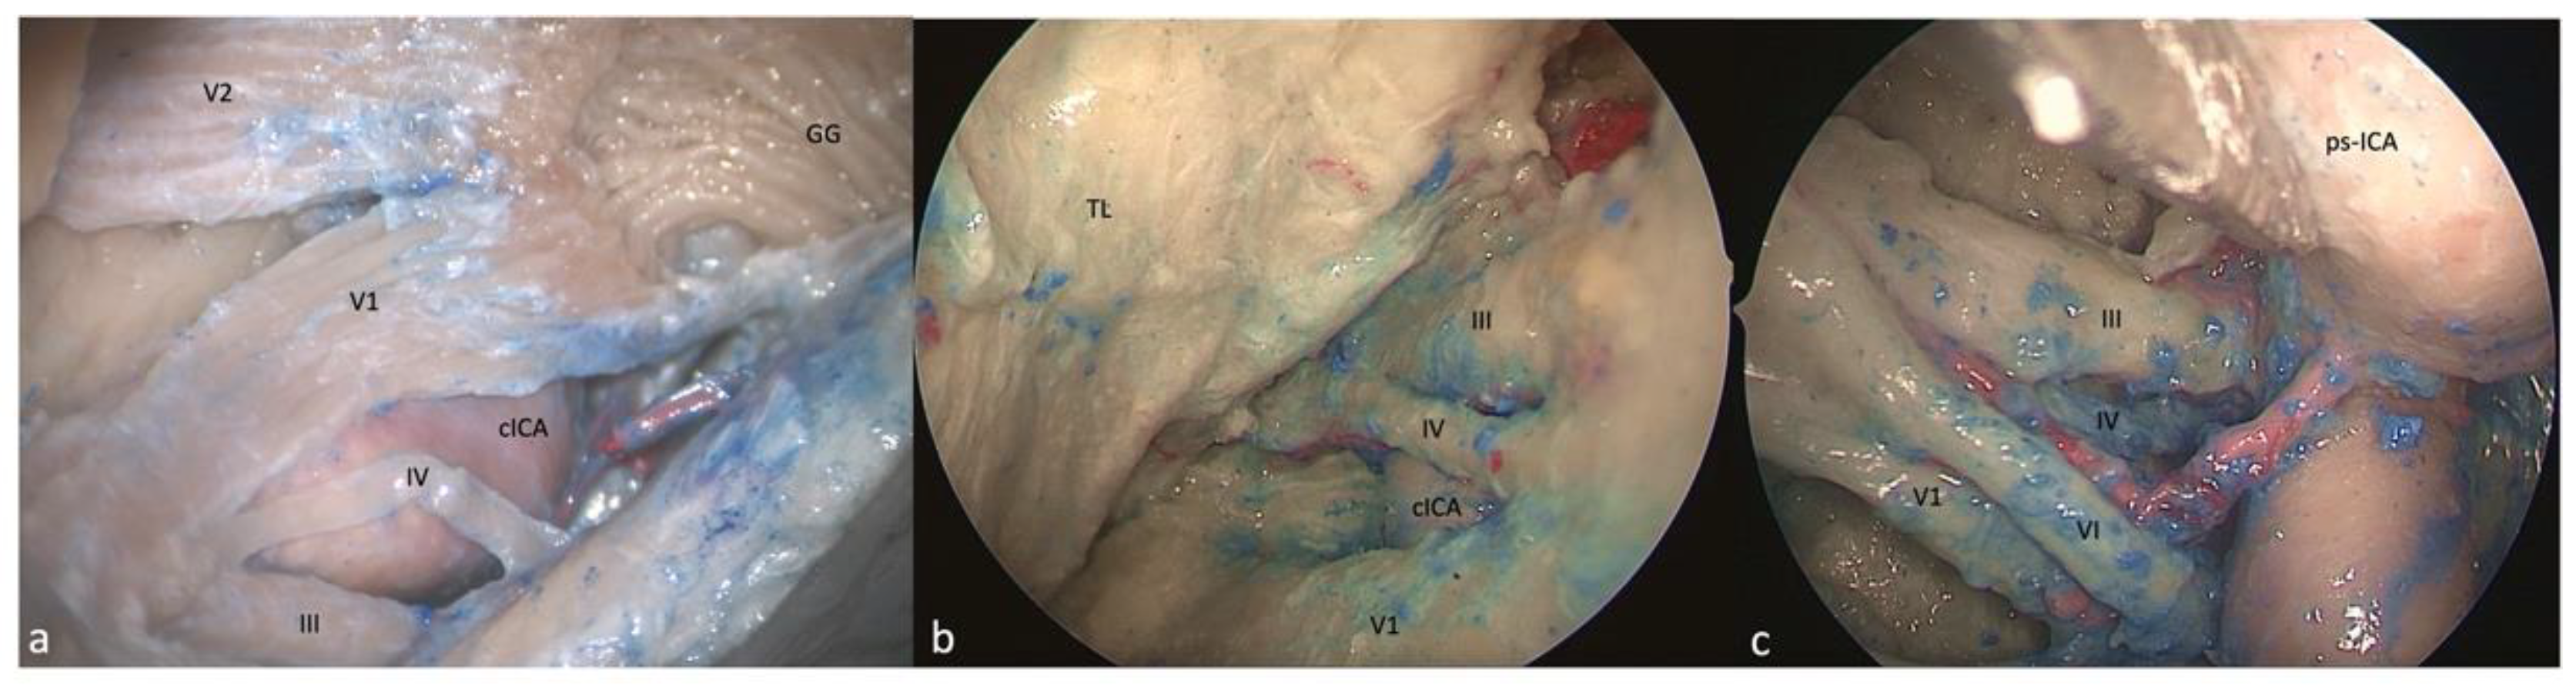

3.1. Clinoid Triangle (Dolenc’s Triangle)

3.1.1. FTOZ Perspective

3.1.2. SETOA Perspective

3.1.3. EEEA Perspective